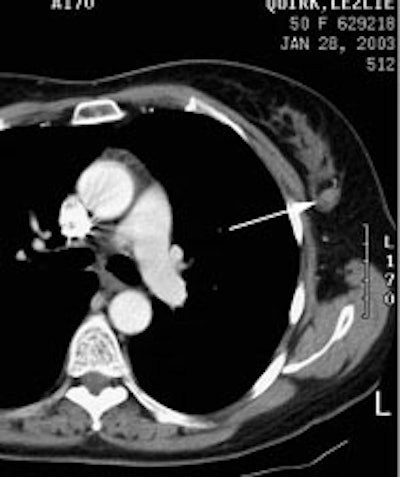

FDG PET exam for the evaluation of locoregional recurrence: The patient shown in the case below had a history of breast cancer and had developed left chest pain. She presented for the evaluation of possible metastatic disease. The CT scan revealed extensive soft tissue thickening in the left breast which was felt possibly related to scar from prior surgery and radiation therapy. There was a 2 cm lymph node in the left axilla (not shown) which was concerning for metastatic disease. Axial (center) and coronal (right) images from the patients FDG PET exam demonstrated marked increased FDG accumulation within the left breast corresponding to the soft tissue abnormality on CT. There were also multiple foci of increased uptake within the the left axilla. Biopsy revealed recurrent breast cancer. Case courtesy of CTI, The power behind PET. |

|